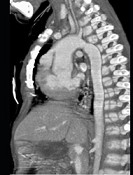

- 多项选择题患者,男性, 8岁,发绀、气促, 易感冒,彩超提示只见一个心室, CT检查如图所示,请选择正确的选项 ( )